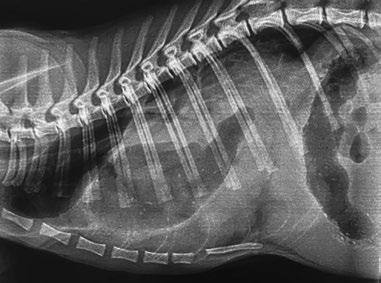

Se presenta el caso de una gata sometida a craneotomía supratemporal para exéresis de un menigioma, en la que se realizó un mantenimiento anestésico intravenoso para mantener una mayor estabilidad hemodinámica durante la cirugía.

Maine Coon, hembra castrada de 8 años, 3,5 kg y condición corporal 5/9, diagnosticada mediante resonancia magnética de una lesión extradural que afectaba a los lóbulos parietal, temporal y occipital (posiblemente meningioma) y que le producía un cuadro de circling, que en el momento de la anestesia estaba controlado gracias al tratamiento con dexametasona 0,15 mg/ kg/24 h. Como otros antecedentes clínicos, la paciente presentaba barro biliar, iniciándose el tratamiento con ácido ursodesoxicólico.